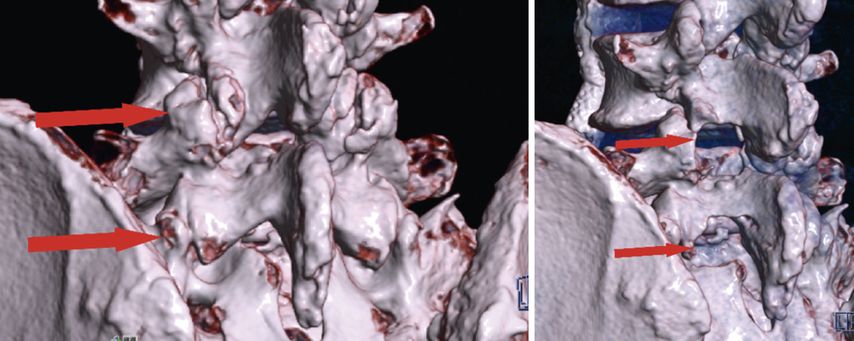

Lumbale vollendoskopische Dekompression

Bei zentraler Spinalkanalstenose und lateraler Rezessusstenose ermöglichen endoskopische Verfahren eine schonende und effektive Dekompression. Eingriffe können unilateral oder bilateral über die Over-the-top-Technik (ULBD) erfolgen. Randomisierte Studien belegen ein funktionell gleichwertiges Outcome im Vergleich zur offenen Dekompression, jedoch bei günstigerem Risikoprofil, kürzerem stationärem Aufenthalt und früherer Mobilisierung.13,19 Bei 161 Patienten mit lateraler Rezessusstenose konnte eine Überlegenheit der vollendoskopischen Operation hinsichtlich Operationszeit, Blutverlust, Komplikationsrate und Revisionshäufigkeit demonstriert werden.19 Am eigenen Patientenkollektiv bei 80 interlaminären vollendoskopischen Dekompressionen konnten 76% der Patienten bereits am Operationstag mobilisiert werden. Über die generellen Vorteile der spinalen Endoskopie hinaus zeigt sich, dass bestimmte Patientengruppen in besonderem Masse profitieren. Hierzu zählen adipöse Patienten, (Leistungs-)Sportler mit dem Bedürfnis nach rascher funktioneller Erholung und minimiertem Gewebetrauma sowie ältere Patienten, bei denen eine erhöhte Invasivität die Mobilisierung weiter einschränken würde und die dadurch profitieren. Abbildung 5 zeigt eine präoperative (linkes Bild) und postoperative (rechtes Bild) 3D-CT-Rekonstruktion nach endoskopischer unilateraler Laminotomie mit bilateraler Dekompression (ULBD) bei L4/5 und L5/S1 (Abb. 5).